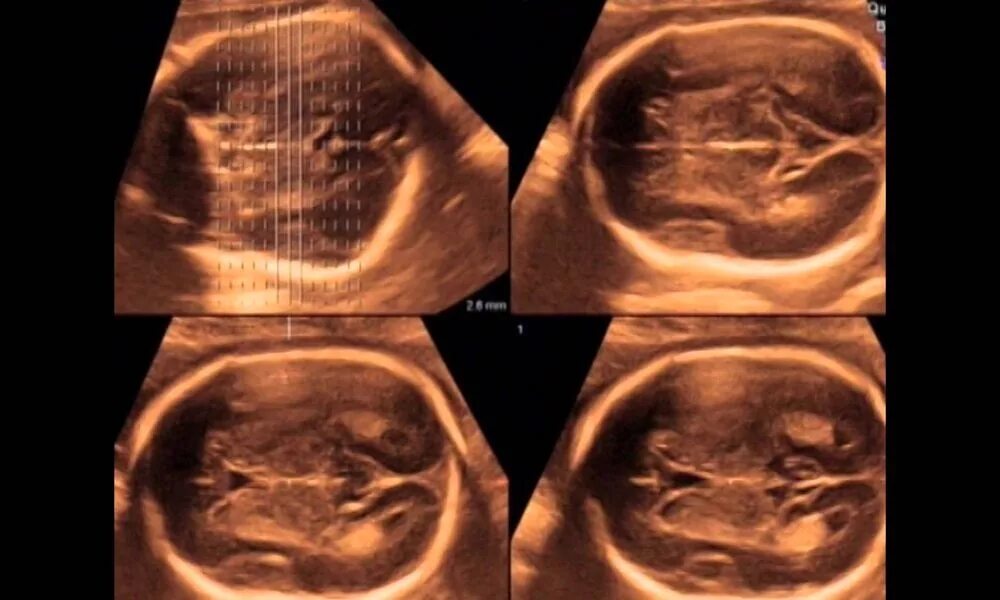

Второй скрининг 21 неделе